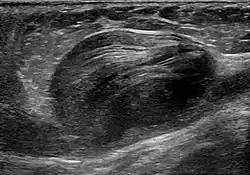

Abdominal aortic aneurysm involves a regional dilation of the aorta and is diagnosed using ultrasonography, computed tomography, or magnetic resonance imaging. A segment of the aorta that is found to be greater than 50% larger than that of a healthy individual of the same sex and age is considered aneurysmal.[9] Abdominal aneurysms are usually asymptomatic but in rare cases can cause lower back pain or lower limb ischemia.